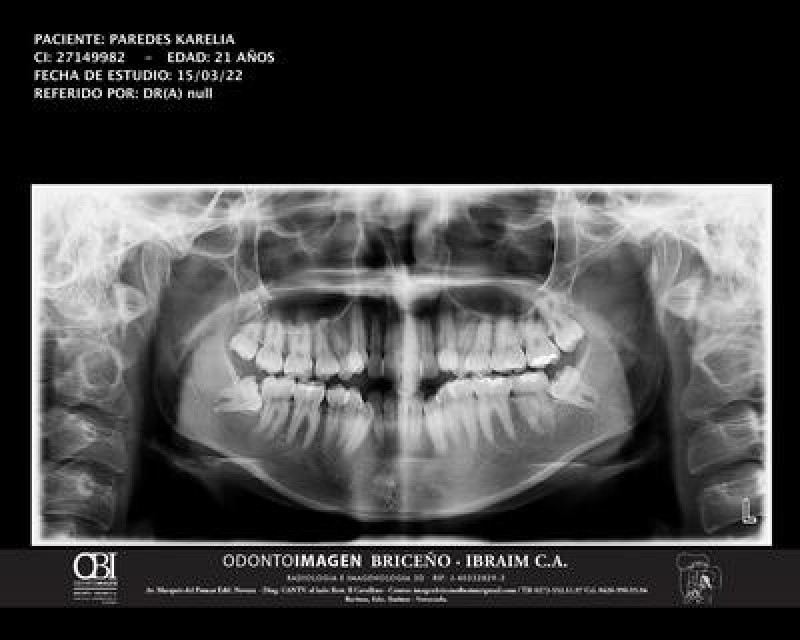

Hi, I decided to seek for monetary help online to pay my personal expenses, most of the jobs that pay a good salary in my city, do not accept students, have a Monday to Sunday schedule, 12 hour shifts (I study on weekends, I'm two years away from graduating in management), so looking for a job becomes constant. In my house my dad is the main provider, my mom is a SAHM, getting a job is very important considering the political, social and economic problems that my country Venezuela has been suffering for years. I was lucky (so to speak) to not have enough space in my mouth to accommodate all my teeth, including wisdom teeth (lucky me), which forces me to seek dental help, going to the dentist is quite expensive in my country thanks to the crisis, and in my case, I require orthodontics (the dentist said 2.5 years) and extraction of 8 teeth in total (between wisdom teeth and premolars). Thanks to my father, I managed to get upper braces and have 2 of 4 wisdom teeth extracted. The operation to remove the two remaining wisdom teeth costs $70 (had to get and appointment with a maxillofacial surgeon for the wisdom teeth), and each premolar extraction costs $20, plus the installation of the lower bracket, costs $30. To be able to pay for and continue my orthodontic treatment is something that I long for, with the help that you can give me, I'll be able to reduce my personal expenses while I continue looking for a job that will not force me to drop out of college, I'll be very grateful to all those who contribute, and I hope I will also be one of the people to help others in my same situation, thank you very much! https://www.paypal.me/KareliaIPL